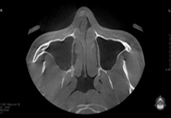

Полная проверка состояния носа благодаря снимкам КТ.

Благодаря 3Д-КТ снимкам возможно рассмотреть в мельчайших подробностях не только состояние костей носа, но и форму, состояние и размеры мягких тканей вокруг него, что позволяет правильно составить безопасный план операции.